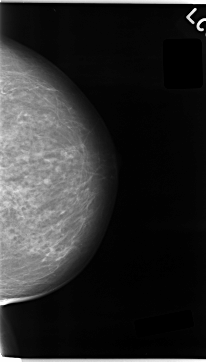

C_0043_1.LEFT_CC

LEFT_CC LINES 4696 PIXELS_PER_LINE 2672 BITS_PER_PIXEL 12 RESOLUTION 50 NON_OVERLAY